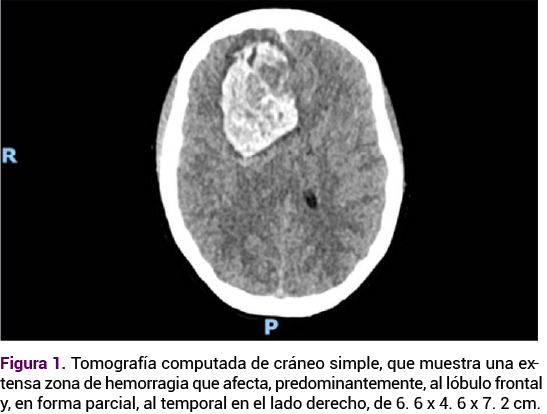

En el quinto día de hospitalización la paciente tuvo un Glasgow de 5 por flexión anómala, postura de decorticación y pupilas isocóricas. El ultrasonido transcraneal y la tomografía de cráneo evidenciaron una nueva hemorragia intracraneal. Durante la estancia en el quirófano sobrevino una hemorragia intracraneal mayor a 30 cc y herniación cerebral en el hemisferio cerebral derecho. Se procedió al drenaje del hematoma intracraneal más plastia dural, lobectomía temporal hasta la base de la fosa media cerebral y apertura de las cisternas en la base. Además, ampliación de la craniectomía, apertura dural y colocación de un drenaje subdural abocado a la base. No se visualizaron nidos de malformación o alteración vascular que justificaran la hemorragia. Se continuó con la vigilancia fetal transoperatoria, con ultrasonido con frecuencia cardiaca fetal entre 119 y 132 lpm, con disminución de los movimientos. La toalla testigo evidenció el sangrado transvaginal y coágulos en moderada cantidad. Al tacto vaginal se encontró con el cuello cerrado, formado y posterior, con sangre en la vagina. Se indicaron 100 mg de indometacina intrarrectal en dosis única.

<strong>Figura 3</strong>

Figura 3. TAC simple de cráneo. Nueva hemorragia intracraneal con efecto de masa y herniación cerebral en el hemisferio derecho.